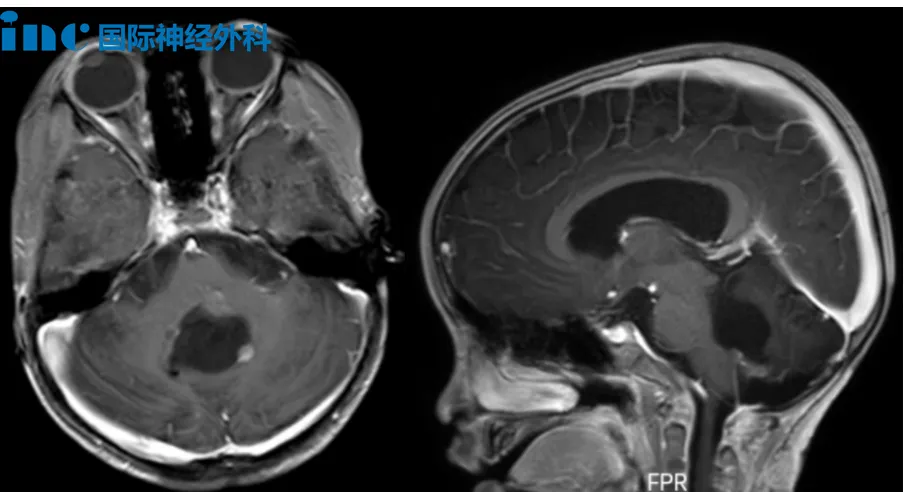

5岁男孩布布,2023年因走路不稳发现颅内占位,于同年9月接受第一次四脑室肿瘤切除手术,术后病理为后颅窝室管膜瘤。2024年5月因肿瘤复发再次接受手术,病理升级为间变性室管膜瘤,WHO 3级。术后布布出现了斜视、眼炎、四肢无力、共济失调、吞咽障碍及言语迟缓等一系列症状。2024年9月完成质子放疗后,近期复查又提示术区边缘出现可疑结节,黏连延髓,疑似再次复发。尽管在治疗过程中,孩子的病情经历了多次挑战,但布布的家人始终没有放弃希望。在得知巴教授来华的消息后,他们希望能为布布争取新的机会。

“幸运的是,肿瘤没有深度侵入脑干内部,而是位于脑干的背侧表面,这意味着这三处病灶在手术上都具有很好的可达性。”当得到巴教授可以手术的评估时,这彷佛绝望中开出的一朵花,让一直揪着心的父母重新看到了希望!